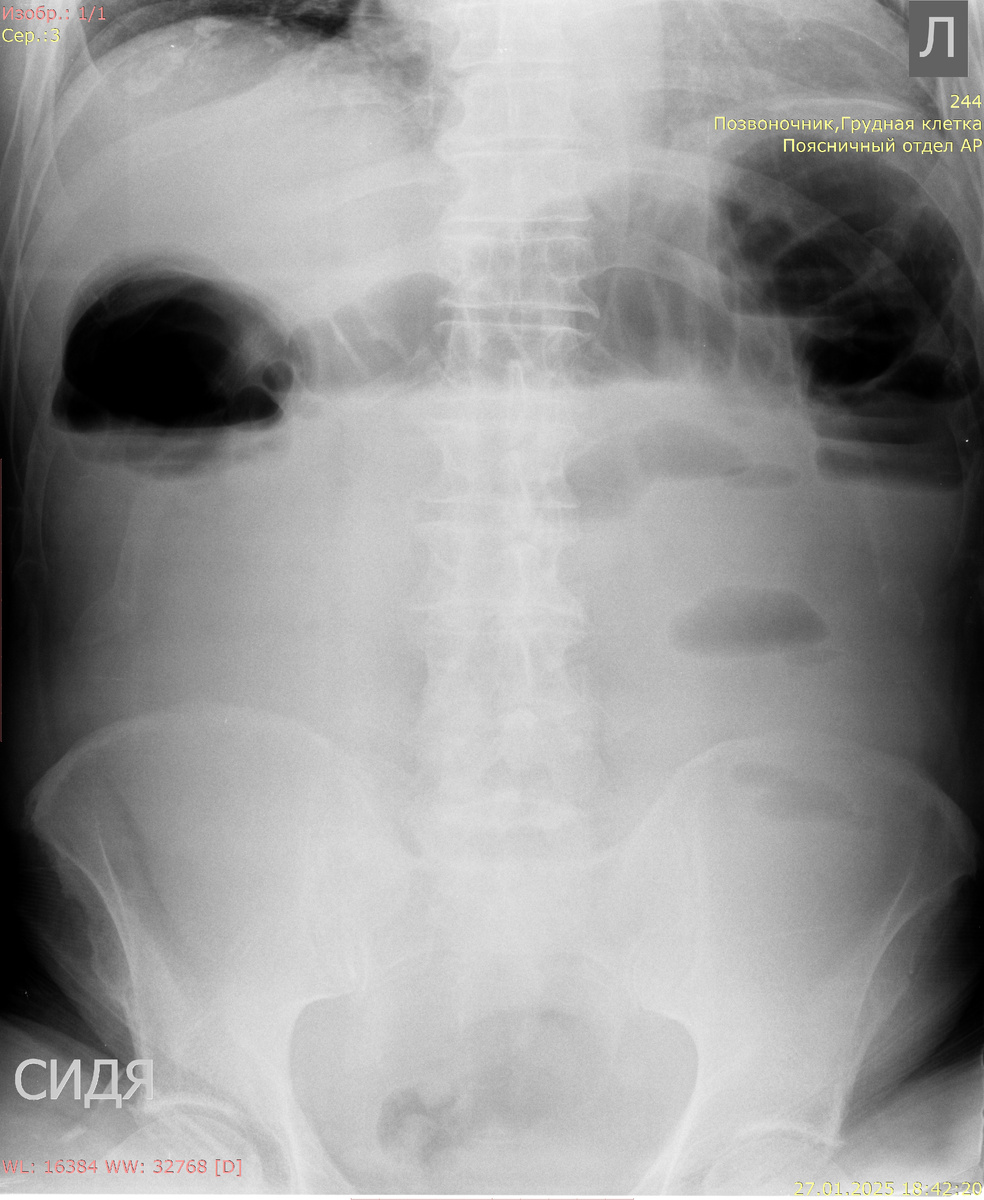

Рентгенологические исследования являются первыми методами, к которым обращаются при подозрении на толстокишечную непроходимость. Они помогают определить наличие или отсутствие этого состояния. На рентгенограммах живота без контраста специалисты используют принцип "дважды обдумать", что подразумевает внимательное исследование общей картины. Врачи обращают внимание на наличие уровня жидкости, расширение кишечных петель, а также на наличие свободного воздуха в брюшной полости, что может указывать на возможную перфорацию кишечника.

На рентгенограммах специалисты могут заметить общие признаки, такие как расширение дистальных отделов кишки и сужение или отсутствие контрастирования в более проксимальных участках. Эти находки позволяют врачам оценить уровень непроходимости и выявить потенциальные причины ее возникновения.

Ширина толстой кишки боле 60 мм - непроходимость.